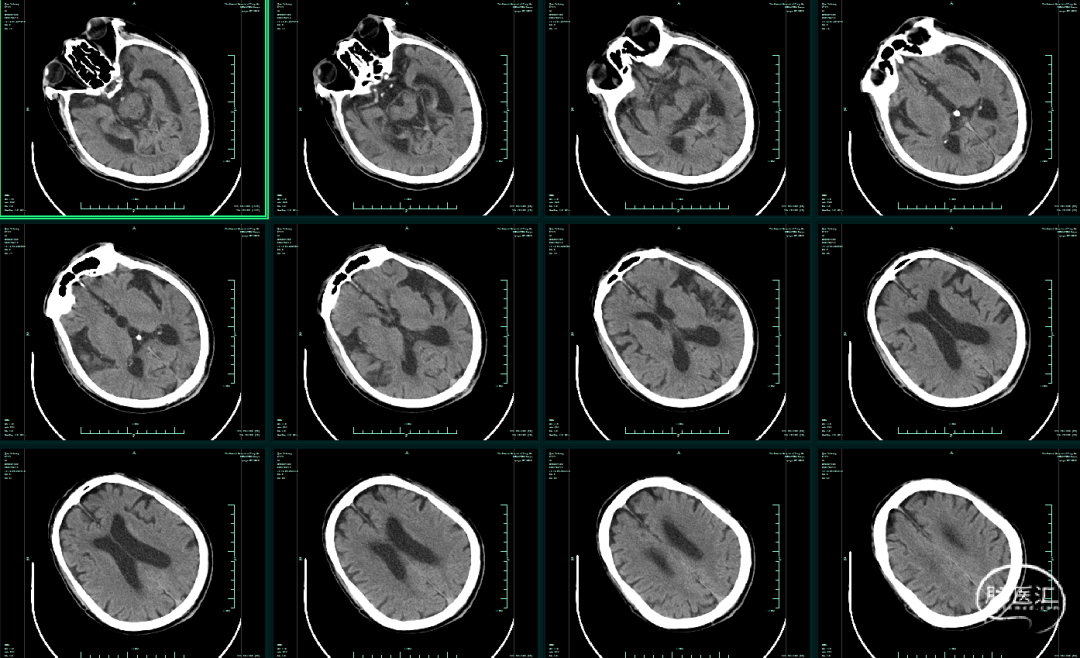

影像学资料

CT平扫未见颅内出血,右侧大脑中动脉高密度影,可疑血栓。

患者意识障碍,左侧肢体偏瘫,NIHSS评分12分。头颅CT:颅内未见出血。DSA:右侧颈内动脉闭塞。发病时间1.5小时。无明确手术禁忌。